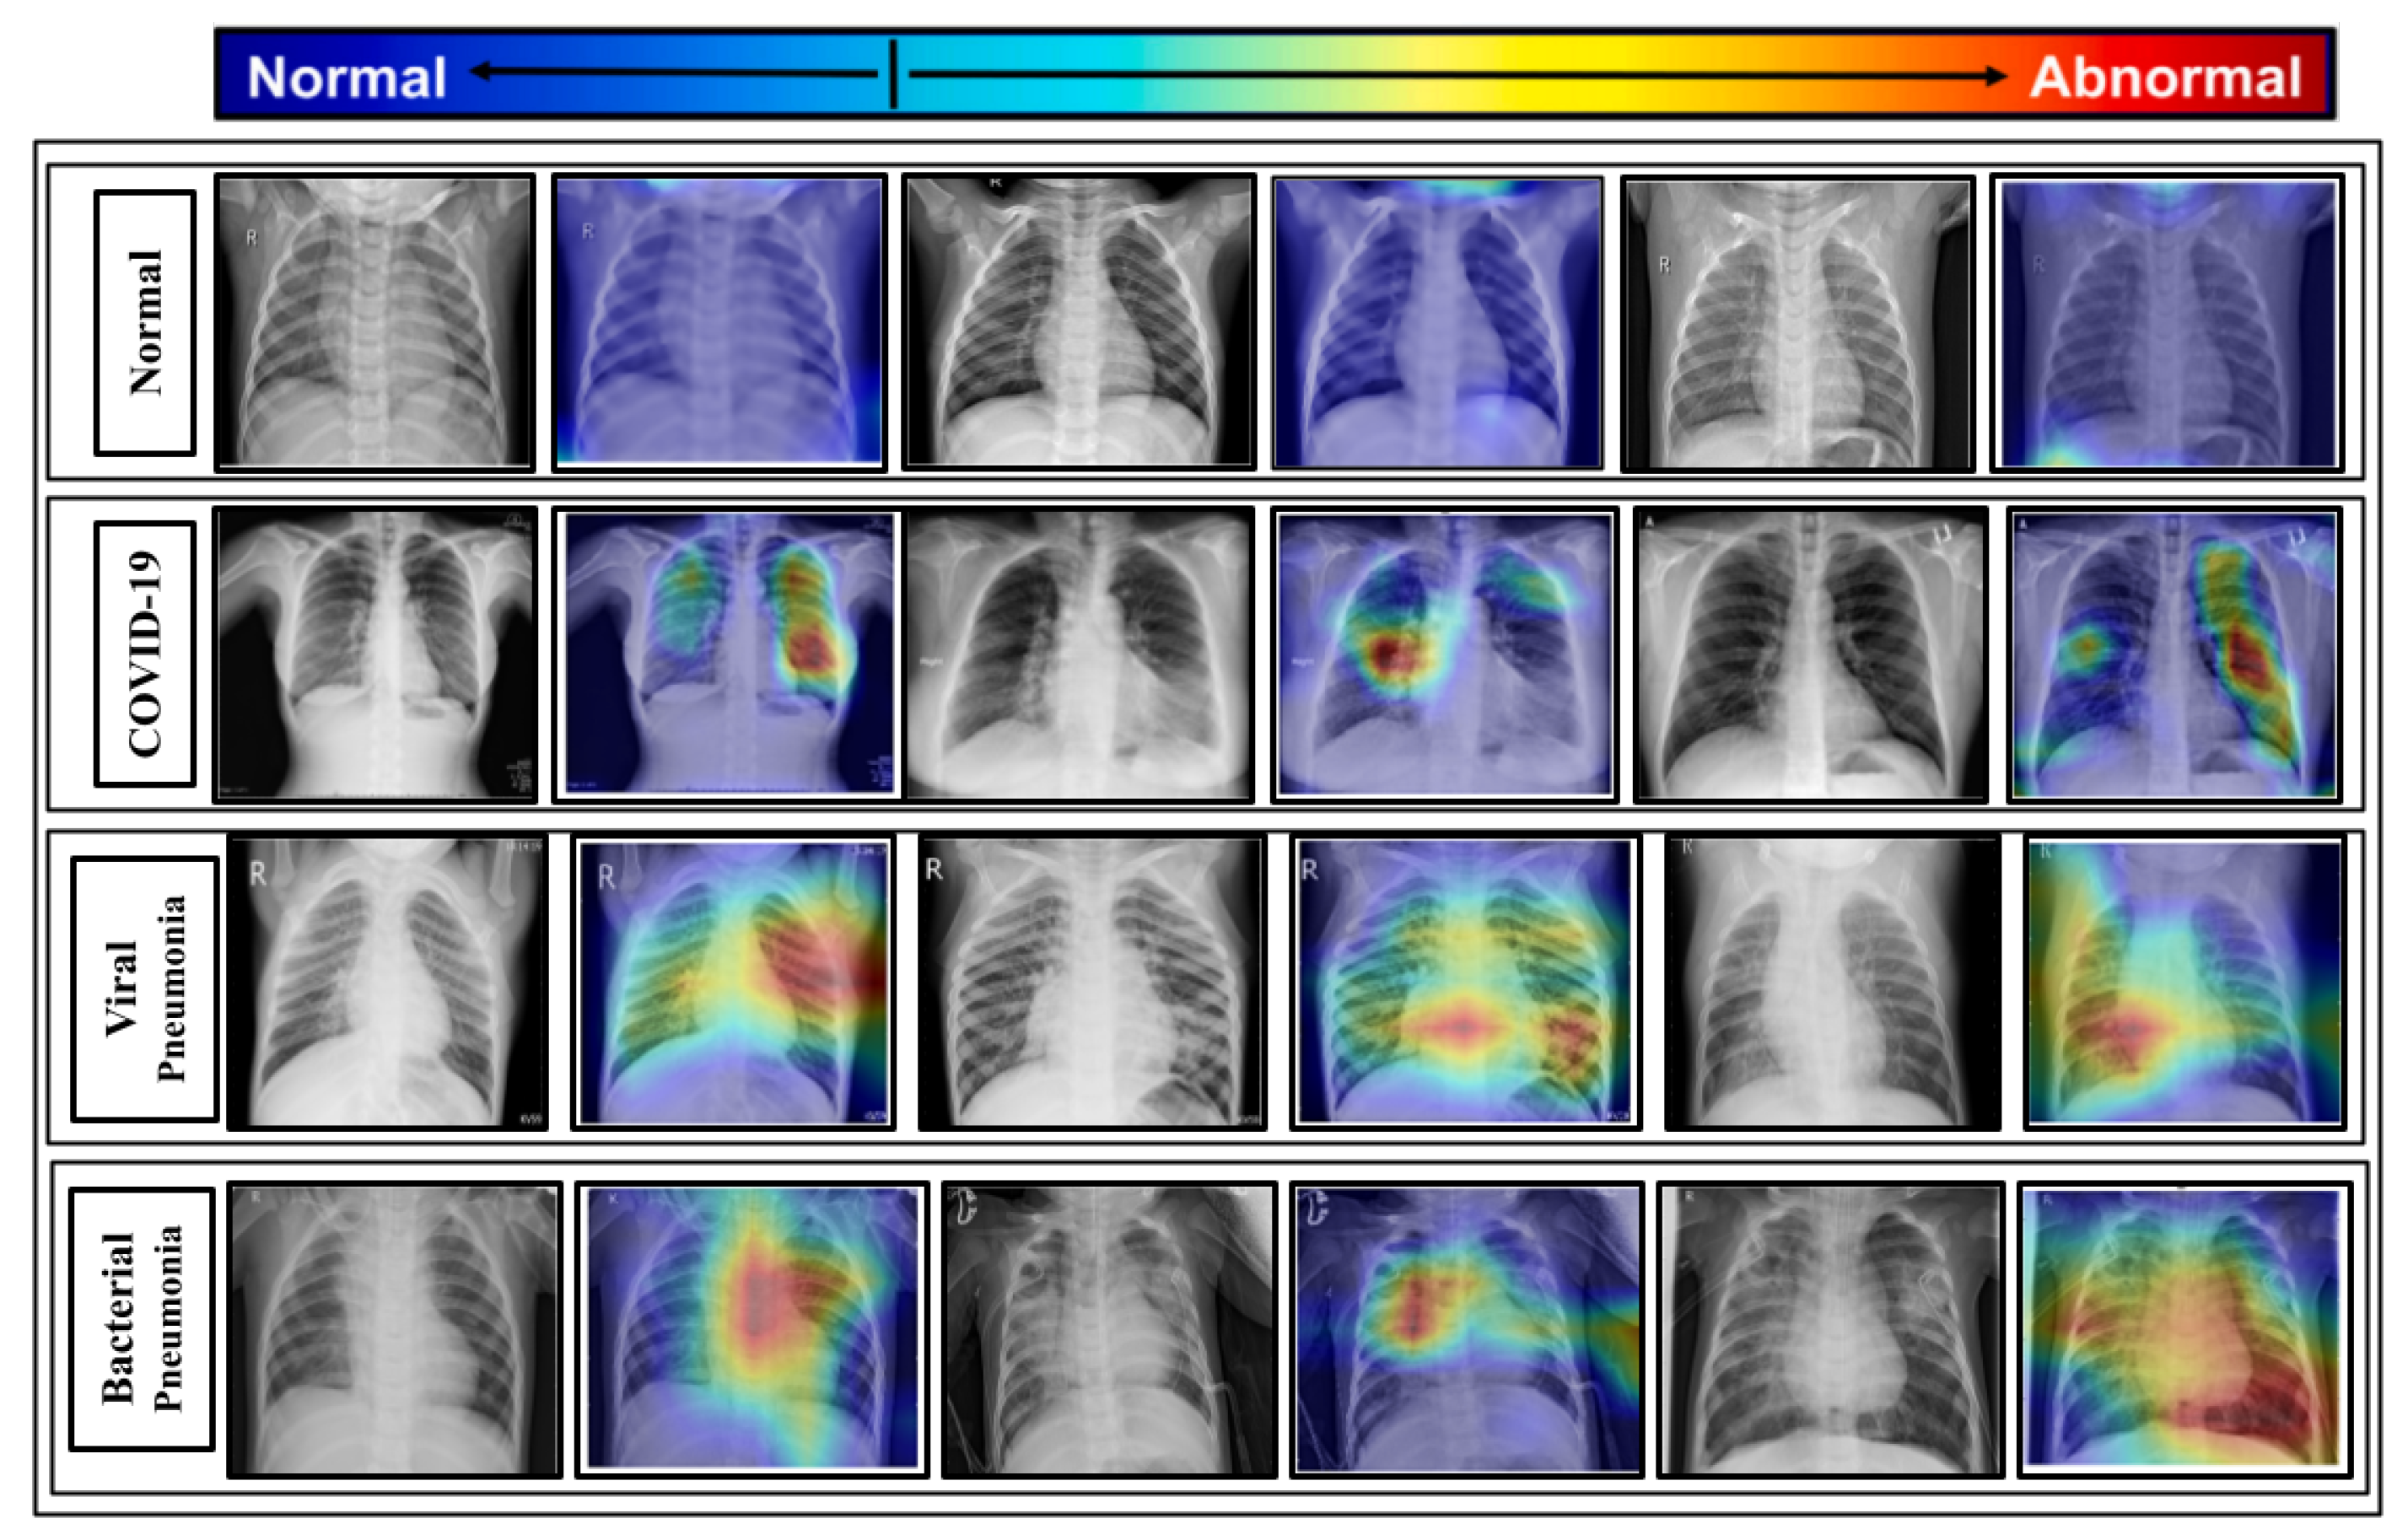

The proposed model is combined with the gradient-based class activation mapping (Grad-CAM) approach [80] to construct the class activation mapping to localize the specific region of the X-rays that mostly prompted the decision, as illustrated in Figure 12.

Figure 12.

Such localizations are further investigated by superimposing the heatmap with the input X-rays to evaluate the network’s learning from a clinical standpoint. Some of the chest X-rays with the imposed localization are displayed in Figure 13.

Figure 13.

Significant portions of the test chest X-rays that induce the decision are localized by imposing the class activation heatmap obtained from the proposed model.

The following are some of the key findings:

- By considering the normal X-rays, there is no opacity in normal X-rays, which distinguishes normal cases from all types of pneumonia cases who have opacities with various types [81,82,83]. For normal X-rays, no substantial region is localized, as shown in Figure 13. Since it is more recognizable, it is easier to distinguish from the other patients.

- When looking at the heatmaps for classical viral pneumonia, it is observed that our proposed model has localized the regions with bilateral multifocal Ground Glass Opacities (GGO) as well as patchy consolidations in some cases. These localized characteristics are also commonly recognized as radiological features of classic viral pneumonia [9,84,85].

- Localized activation heatmaps in the event of bacterial pneumonia generally involve opacities with consolidation on the lower and upper lobes. Furthermore, both unilateral and bilateral, as well as peripheral, participation is seen. These characteristics, according to [81,82], are primarily associated with bacterial pneumonia.

- According to [9,85], COVID-19 and typical viral pneumonia have many similarities, including bilateral GGOs and patchy consolidations. Peripheral and diffuse distributions, vascular thickening, micro-reticular opacity, and typical viral-like Ground Glass Opacities (GGOs) are some of the more likely hallmarks of COVID-19-induced pneumonia [86,87]. By closely inspecting the generated heatmap from several COVID-19 infected X-rays (Figure 13), it is observed that the opacities are distributed in a peripheral and diffuse manner. Furthermore, vascular thickening, as well as other conventional viral features, is localized in some of the cases.